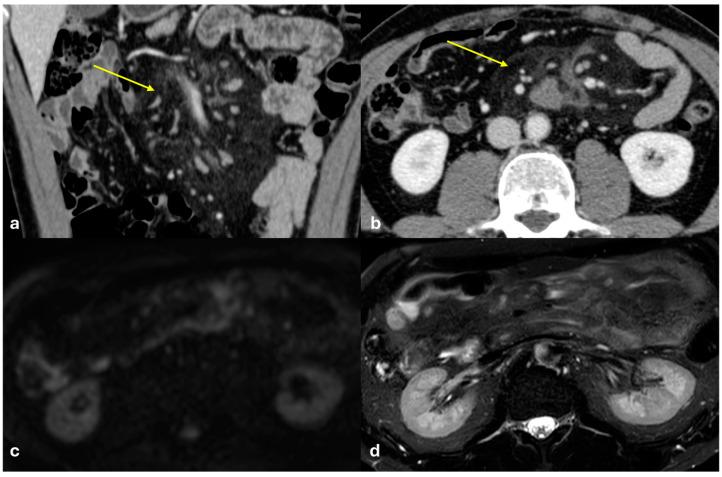

The peritoneum is a thin membrane that lines the abdominal cavity and covers the abdominal organs. It serves as a conduit for the spread of various pathological processes, including gas and fluid collections, inflammation, infections, and neoplastic conditions. Peritoneal carcinomatosis is the most common and well-known pathology involving the peritoneum, typically resulting from the dissemination of gastrointestinal and pelvic malignancies. However, numerous benign and malignant peritoneal diseases can mimic the imaging appearance of peritoneal carcinomatosis. The aim of this review is to revisit the anatomy of peritoneal compartments and elucidate the patterns of peritoneal disease spread. Emphasis is placed on identifying the distinctive imaging features of both neoplastic and non-neoplastic peritoneal diseases that differ from peritoneal carcinomatosis.

腹膜是一层薄的膜,它衬于腹腔内并覆盖腹部器官。它是各种病理过程扩散的通道,包括气体和液体聚集、炎症、感染及肿瘤性疾病。腹膜癌病是涉及腹膜的最常见且广为人知的病理情况,通常由胃肠道和盆腔恶性肿瘤的播散引起。然而,许多良性和恶性腹膜疾病可模仿腹膜癌病的影像学表现。本综述的目的是重新审视腹膜腔室的解剖结构并阐明腹膜疾病的扩散模式。重点在于识别与腹膜癌病不同的肿瘤性和非肿瘤性腹膜疾病的独特影像学特征。